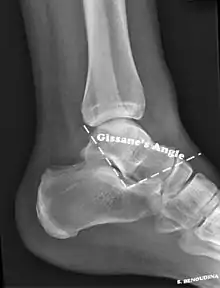

Bohler's angle[14]

Gissane's angle

The Angle of Gissane, or "Critical Angle", is the angle formed by the downward and upward slopes of the calcaneal superior surface. On a lateral radiograph, an angle of Gissane > 130° suggests fracture of the posterior subtalar joint surface. Böhler's angle, or the "Tuber Angle", is another normal anatomic landmark seen in lateral radiographs. It is formed by the intersection of 1) a line from the highest point of the posterior articular facet to the highest point of the posterior tuberosity, and 2) a line from the former to the highest point on the anterior articular facet. Böhler's angle is normally 25° to 40°.[14] It is named after Austrian physician Lorenz Böhler.[16] A decreased angle is indicative of a calcaneal fracture.